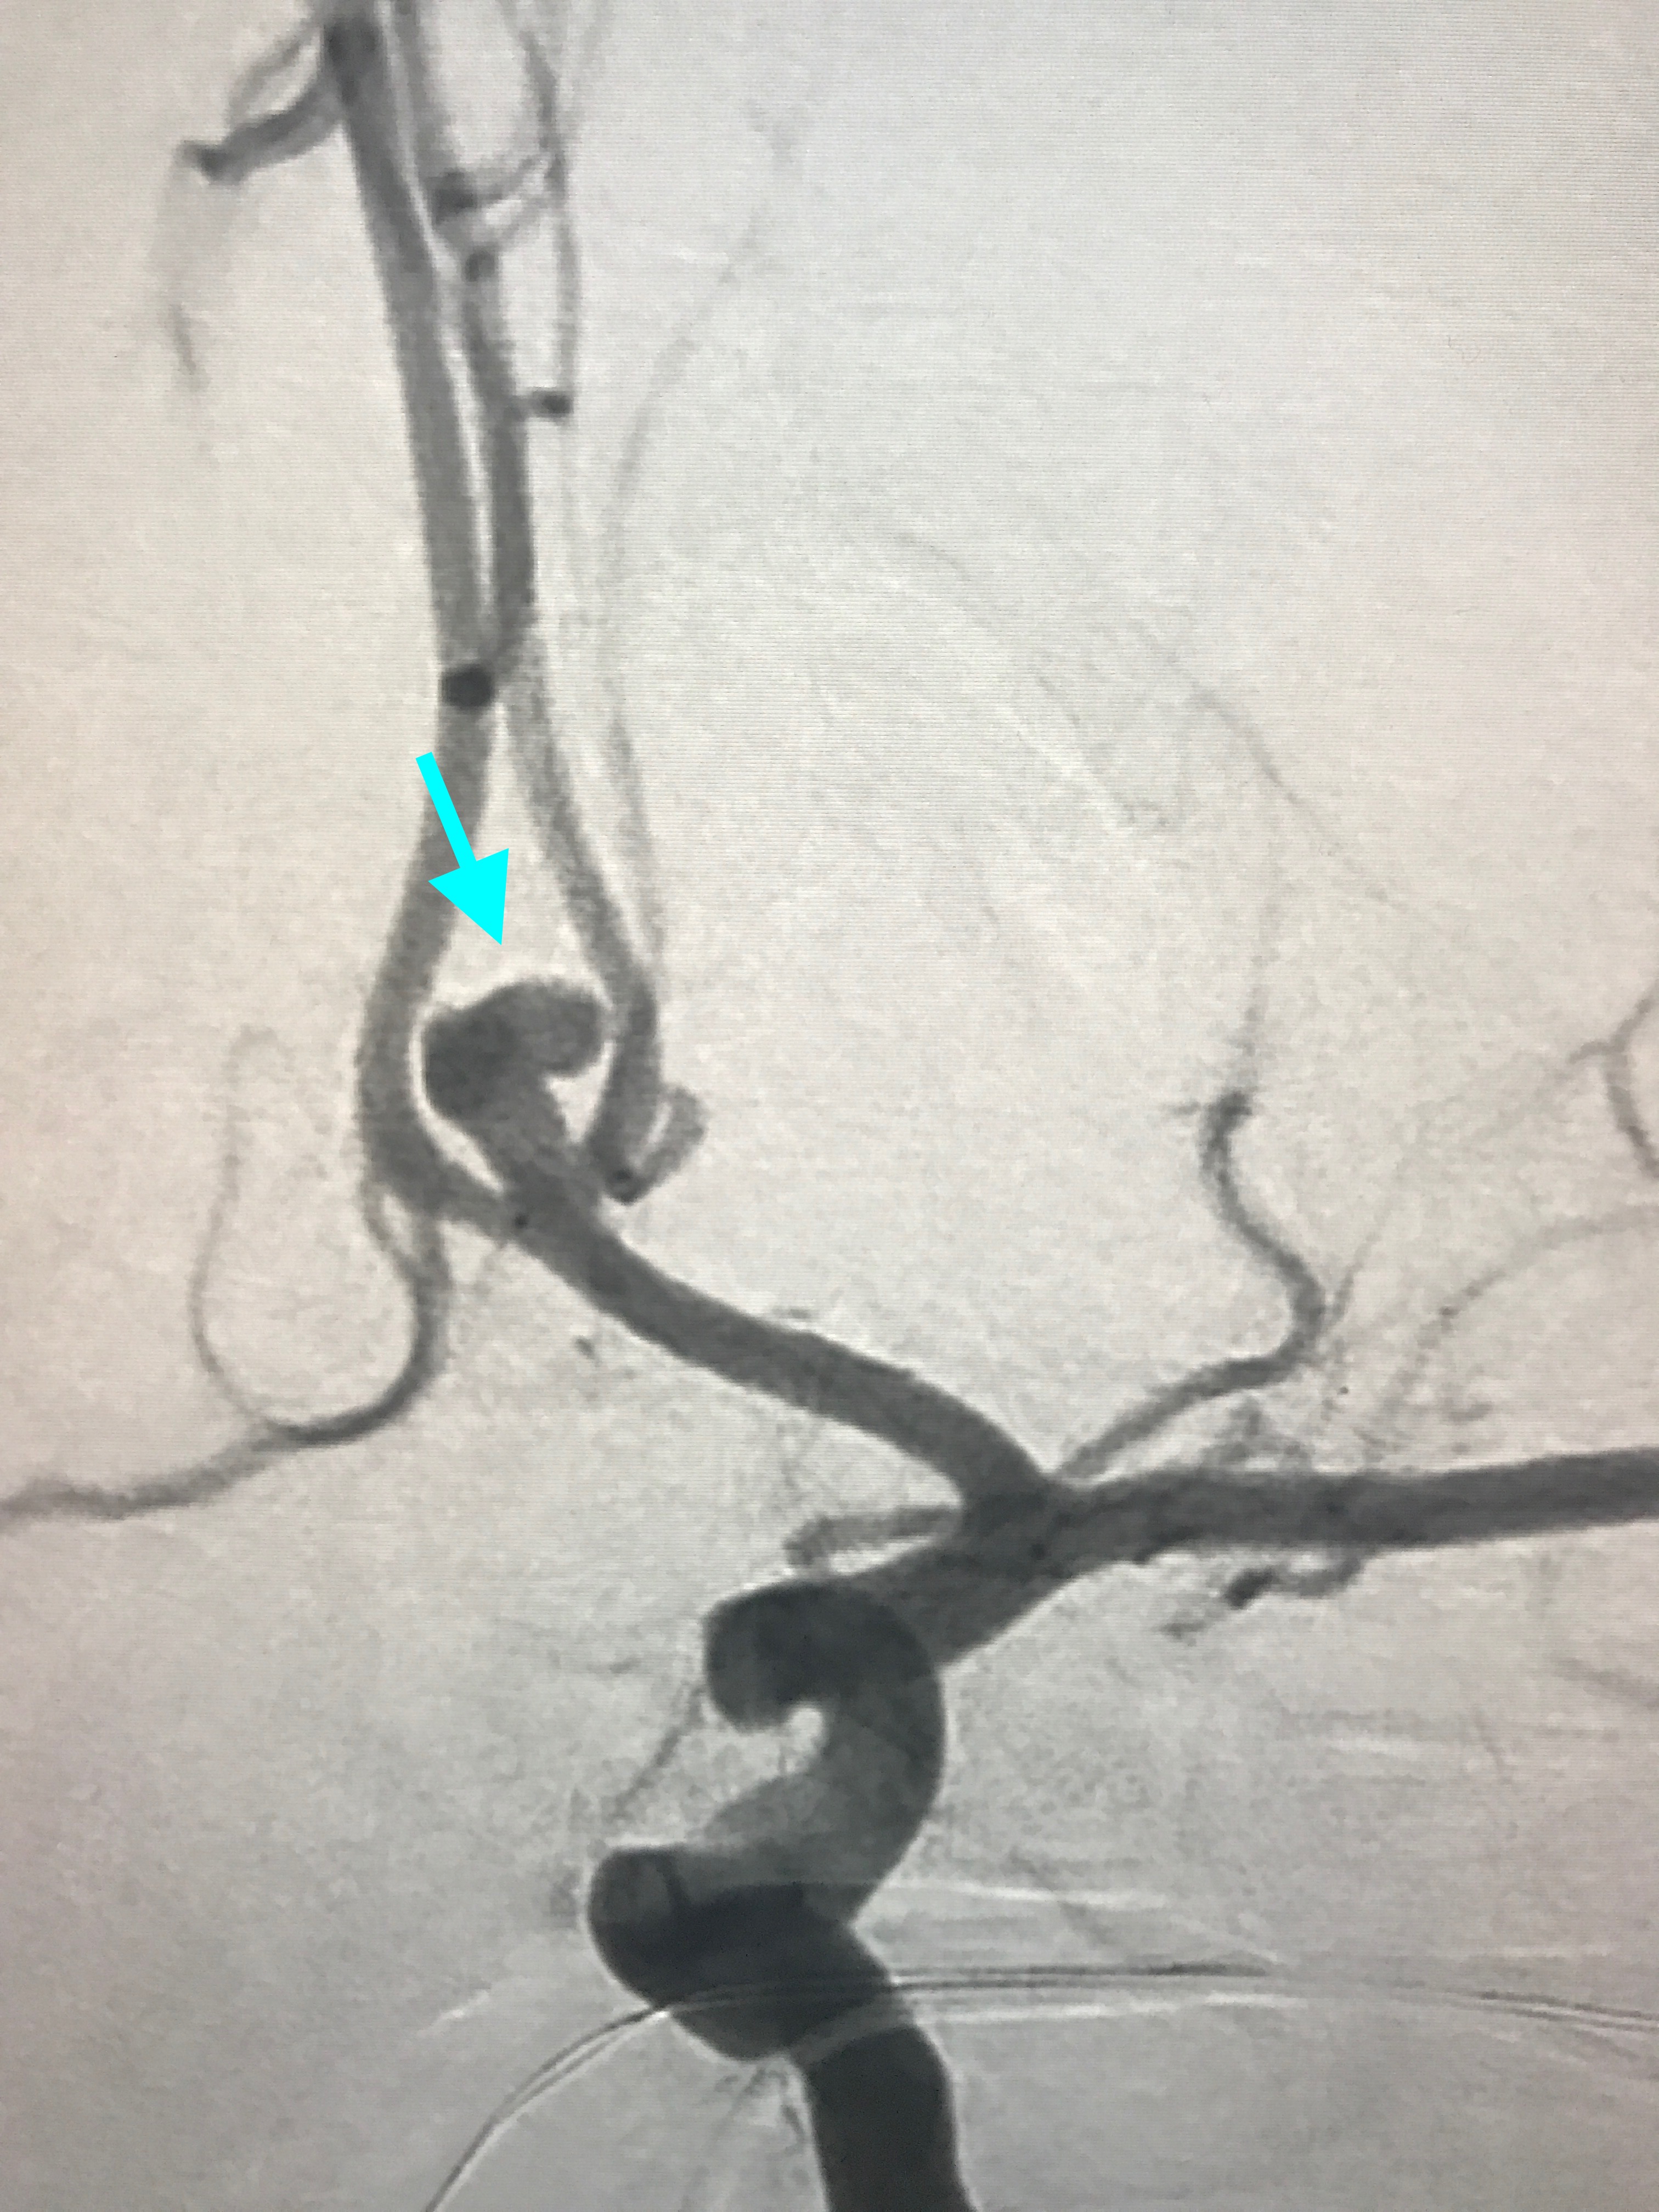

The Myth That Small Brain Aneurysms Don’t Rupture